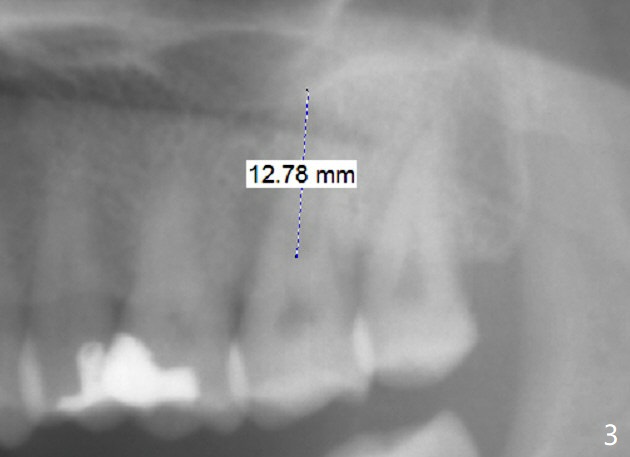

A 54-year-old woman has had palatal root fracture at #15 for several years (Fig.1,2) and finally accept extraction and immediate implant (Fig.3,4). For better trajectory and less screw loosening and crown fracture, guide will be fabricated.